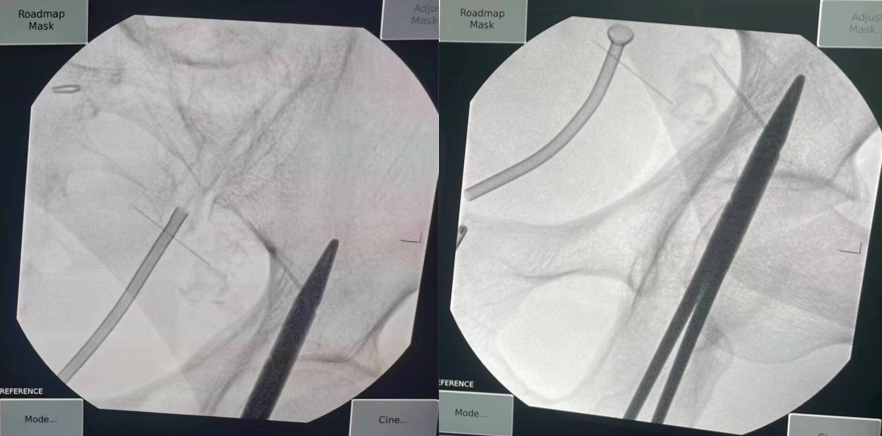

浦金贤主任和沈罡主任在调整支架定位

金属支架置入过程中

我院泌尿外科团队通过精准定位,测量出输尿管狭窄段的长度,将适合长度的记忆金属支架,经人体自然通道无创置入患者输尿管狭窄段。注入65℃热水后,镍钛合金支架成功膨胀,锚定于狭窄处,输尿管再度恢复通畅。术后第二天,患者便能下床活动,手术获得成功。